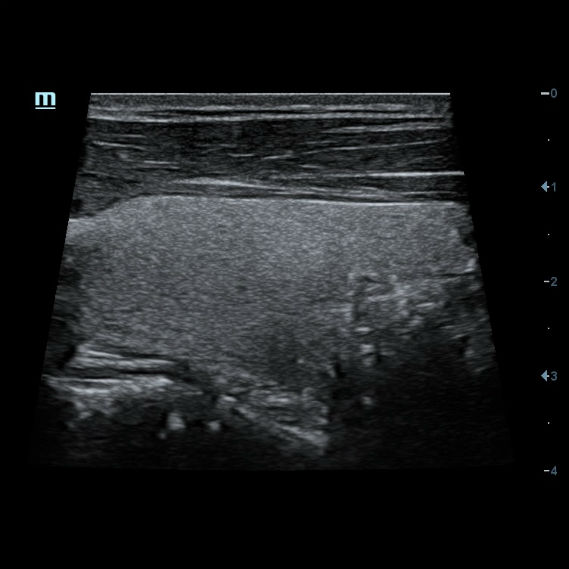

Нажав кнопку iScape мы просто проводим датчик вдоль оси сканирования, и прибор сопоставляет сканируемые изображения в единую, практически бесконечно длинную картину. Теперь влезет всё и продольное сечение щитовидной железы, и широкие гематомы, и крупные кисты Бейкера, и ахиллово сухожилие во всю длину с подробным указанием точек надрыва и указанием расстояния от пяточной кости для уточнения топики травмы даже при изгибе контактной поверхности.